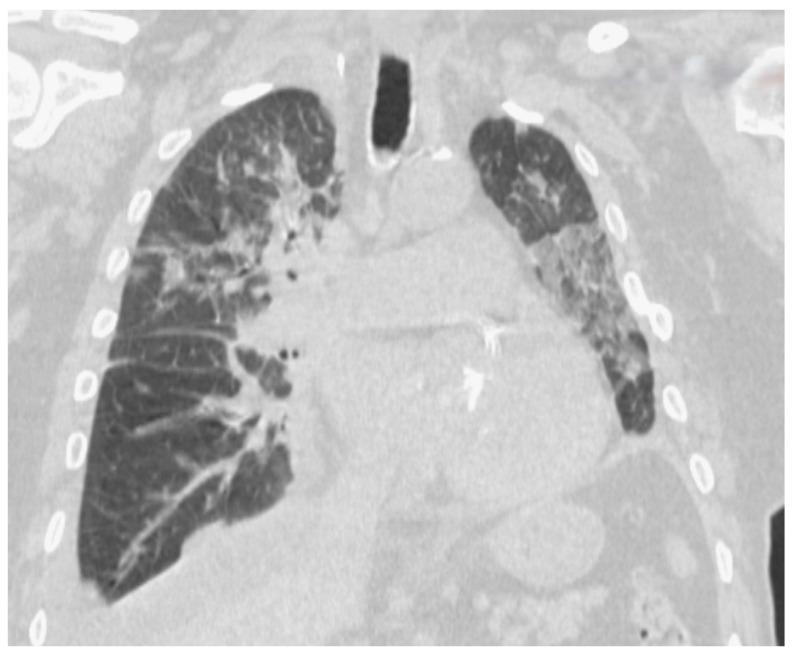

: The newly emergent COVID-19 pandemic involved primarily the respiratory system and had also major cardiovascular system (CVS) implications, revealed by acute myocardial infarction (AMI), arrhythmias, myocardial injury, and thromboembolism. CVS involvement is done through main mechanisms-direct and indirect heart muscle injury, with high mortality rates, worse short-term outcomes, and severe complications. AMI is the echo of myocardial injury (revealed by increases in CK, CK-MB, and troponin serum markers-which are taken into consideration as possible COVID-19 risk stratification markers). When studying myocardial injury, physicians can make use of imaging studies, such as cardiac MRI, transthoracic (or transesophageal) echocardiography, coronary angiography, cardiac computed tomography, and nuclear imaging (which have been used in cases where angiography was not possible), or even endomyocardial biopsy (which is not always available or feasible). We present the cases of two COVID-19 positive male patients who were admitted into the Clinical Department of Cardiology in "Sfântul Apostol Andrei" Emergency Clinical Hospital of Galați (Romania), who presented with acute cardiac distress symptoms and have been diagnosed with ST elevation AMI. The patients were 82 and 57 years old, respectively, with moderate and severe forms of COVID-19, and were diagnosed with anteroseptal left ventricular AMI and extensive anterior transmural left ventricular AMI (with ventricular fibrillation at presentation), respectively. The first patient was a non-smoker and non-drinker with no associated comorbidities, and was later discharged, while the second one died due to AMI complications. From this two-case series, we extract the following: old age alone is not a significant risk factor for adverse outcomes in COVID-19-related CVS events, and that the cumulative effects of several patient-associated risk factors (be it either for severe forms of COVID-19 and/or acute cardiac injury) will most probably lead to poor patient prognosis (death). At the same time, serum cardiac enzymes, dynamic ECG changes, along with newly developed echocardiographic modifications are indicators for poor prognosis in acute cardiac injury in COVID-19 patients with acute myocardial injury, regardless of the presence of right ventricular dysfunction (due to pulmonary hypertension).

新出现的新冠疫情主要累及呼吸系统,也对心血管系统有重大影响,表现为急性心肌梗死(AMI)、心律失常、心肌损伤和血栓栓塞。心血管系统受累是通过主要机制——直接和间接心肌损伤实现的,死亡率高,短期预后差,并发症严重。AMI是心肌损伤的反映(通过肌酸激酶(CK)、肌酸激酶同工酶(CK-MB)和肌钙蛋白血清标志物升高来揭示,这些被视为可能的新冠风险分层标志物)。在研究心肌损伤时,医生可以利用影像学检查,如心脏磁共振成像(MRI)、经胸(或经食管)超声心动图、冠状动脉造影、心脏计算机断层扫描和核成像(在无法进行血管造影的情况下使用),甚至心内膜心肌活检(并非总是可用或可行)。我们介绍了两名新冠阳性男性患者的病例,他们被收治入罗马尼亚加拉茨“圣使徒安德烈”急诊临床医院心内科,出现急性心脏不适症状,并被诊断为ST段抬高型AMI。患者分别为82岁和57岁,患有中度和重度新冠,分别被诊断为前间隔左心室AMI和广泛前壁透壁性左心室AMI(入院时伴有心室颤动)。第一名患者不吸烟、不饮酒,无相关合并症,后来出院,而第二名患者因AMI并发症死亡。从这个两例系列中,我们得出以下结论:仅年龄大并非新冠相关心血管事件不良结局的重要危险因素,几种与患者相关的危险因素(无论是严重新冠形式和/或急性心脏损伤)的累积效应很可能导致患者预后不良(死亡)。同时,血清心脏酶、动态心电图变化以及新出现的超声心动图改变是新冠合并急性心肌损伤患者急性心脏损伤预后不良的指标,无论是否存在右心室功能障碍(由于肺动脉高压)。